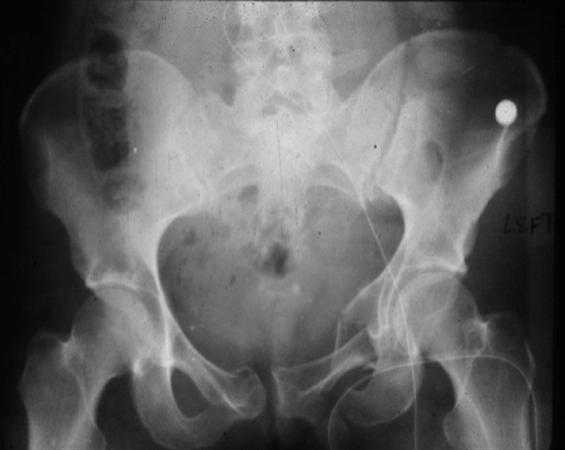

LC (Lateral compression)는 anterior injury가 rami 에서 시작되는 형태입니다.

LC I : sacral fracture 가 같은 쪽에 생깁니다.

LC II : crescrent fracure 가 같은쪽에 생깁니다.

LC III : I+II+ 반대쪽 open book injury 가 동반됩니다.